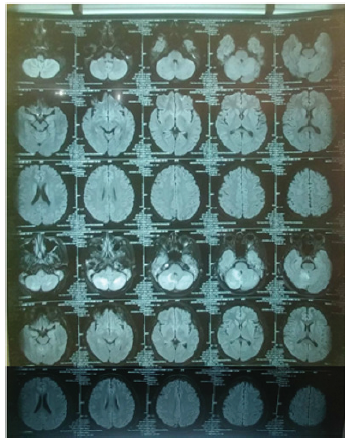

Physical examination showed a good patient consciousness with GCS of 456, right hemiparese with the upper limb and lower limb power were 2 and 4 respectively, and presence of smelly yellowish discharge in both ears. Weber test showed no lateralization and Rinne was negative. The discharge culture result showed colony of Pseudomonas aeruginosa sensitive with gentamycin, ceftazidime, and meropenem, but resistance to ciprofloxacin and levofloxacin. The discharge Ziehl Neelsen test and Gene expert result showed negative result. Sputum gene expert result also showed negative result. Chest X ray and sputum examination gen expert didn’t detect tuberculosis infection (Figure 1). Head contrast MRI showed multiple lesions in cerebellum, right parietal lobe, and left occipital lobe accompanied by cerebral edema, suggestive of cerebral abscess (Figure 2). We have given intravena antibiotik for management of cerebral abscess for 14 days but there is no clinical improvement, we performed head MR spectoscopy and suggested cerebral tuberculosis with increased lactate, NAA degradation, and increased choline/creatine ratio in lesion (Figure 3). The administration of HRZS (Isoniazid, Rifampicin, pyrazinamide, streptomycin) oral anti tuberculosis therapy according to the guidelines for intracranial TB therapy gave satisfactory results with clinical and radiological improvement.

MR Spectroscopy result showed isointenseT1W1 intraaxial lesion, hyper intense T2W1/FLAIR at non restricted central DWI, some with SWI blooming, Multiple in the right and left cerebellum hemisphere and in the right parietal lobe subcortex which worsen the rim after contrast administration. The largest diameter was 8.2 mm in right cerebellum hemisphere. There was lipid degradation, increased lactate, NAA degradation, and increased choline/ creatine ratio in lesion, compared to the perilesion tissue. Furthermore, multiple intraaxial lesions were found in bilateral cerebellum hemisphere and right sub cortex suspected with tuberculoma (improved), bilateral chronic mastoiditis (fixed) (Figure 2).